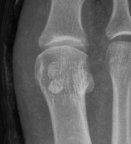

Imaging

Bilateral standing xray can help

Unclear if bipartite or stress fracture

Irregular borders suggest fracture rather than bipartite

CT demonstrates irregular borders consistent with fracture of tibial sesamoid